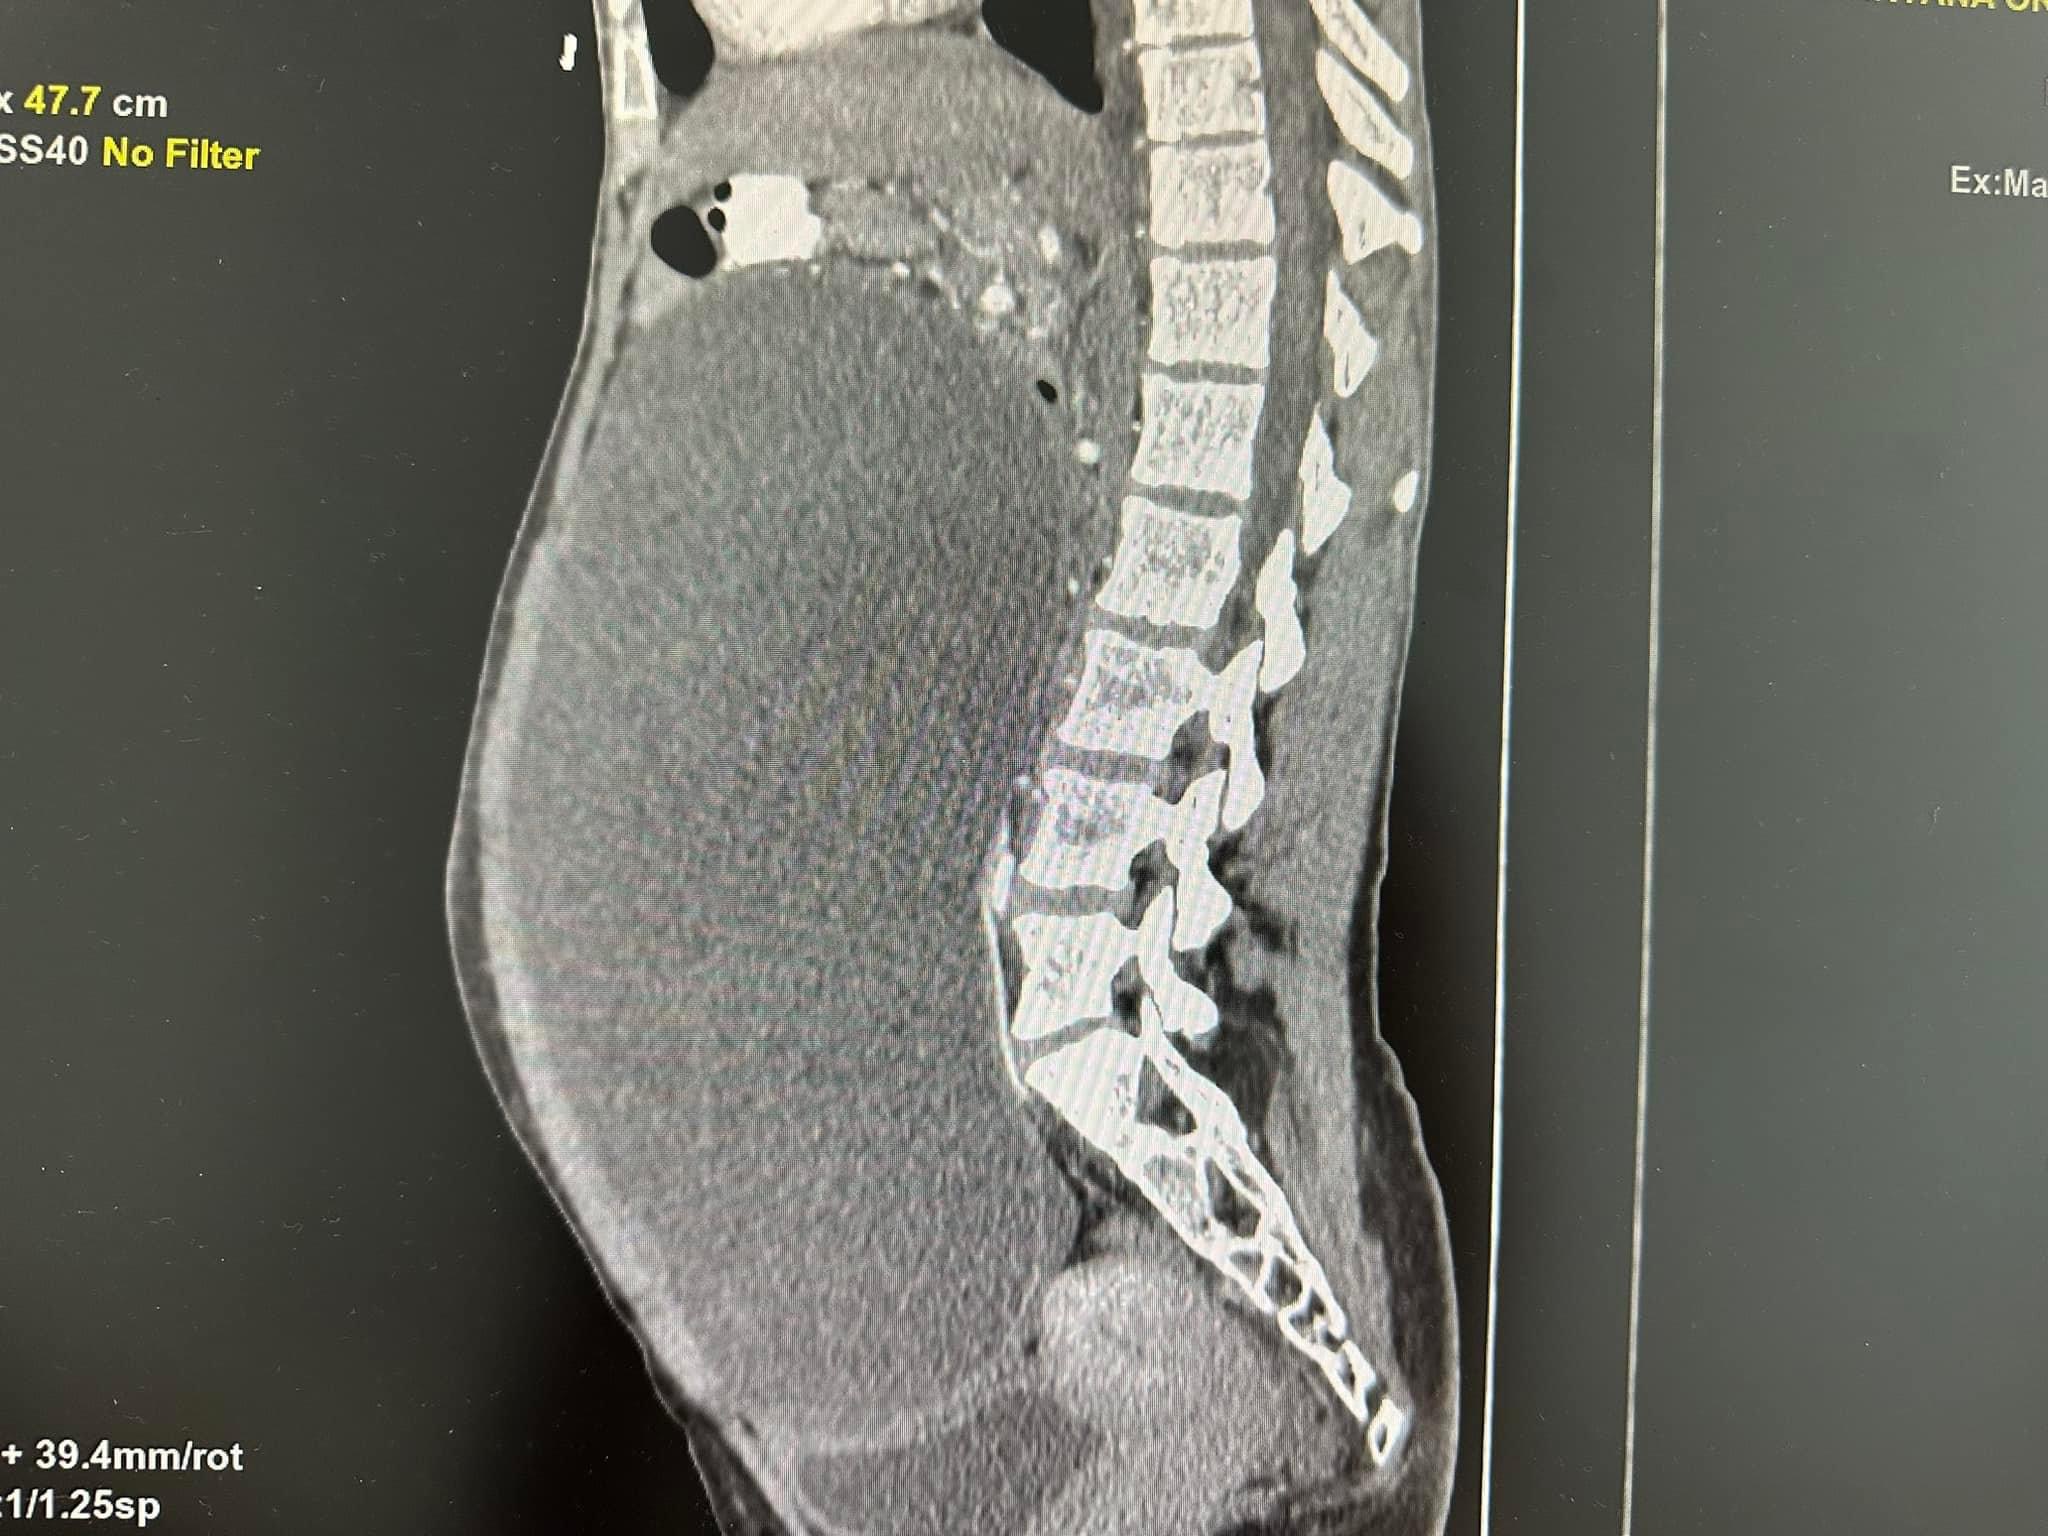

Жінка прийшла до спеціалістів лікарні святого Пантелеймона. Під час УЗД та КТ-обстеження медики виявили величезний новоутвір, розміром 20 на 25 см. Він займав уже всю черевну порожнину пацієнтки. Це була кістома – доброякісна пухлина, що утворюється з епітелію яєчника. По суті, це капсула, що заповнена всередині рідиною. Такі утвори дуже стрімко ростуть і можуть перетворюватися на злоякісні. Тож єдине можливе лікування – це видалення пухлини.

Операція була плановою. Лікарі – завідувачка гінекологічного відділення лікарні святого Пантелеймона Оксана Непийвода та акушер-гінеколог Тарас Бучинський успішно виконали лапароскопічну цистектомію. Вони видалили кістому через три розрізи по півтора сантиметра кожен. І забрали з неї ціле відро рідини – аж 9 літрів. А потім видалили і саму капсулу – лише вона важила 1,5 кг.